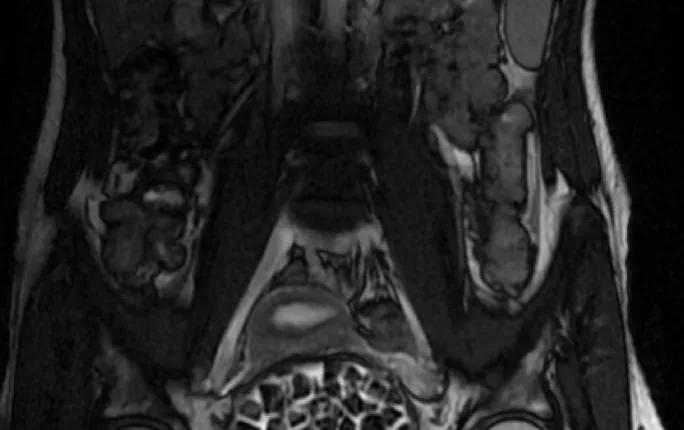

Turkish Doctors Remove 287 Stones From Young Woman

In Türkiye, 21-year-old Fatma Nur Öztürk underwent surgery after severe abdominal pain revealed a rare condition. Doctors discovered and removed 287 stones, the largest measuring 2.5 centimeters, from her bladder and vaginal area.